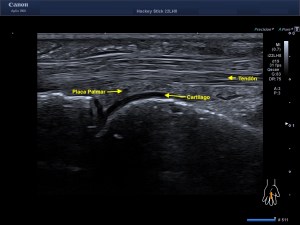

La radiografía revela aumento de las partes y se refrenda en la ecografía como puedes ver en la imagen aunque aún no hay afectación en el hueso en el caso que te presento hoy.

Ecografícamente y debido a su levedad, en el caso de hoy solo observamos cambios en las partes blandas de la cara lateral de la cabeza del quinto metatarsiano, este tejido se muestra heterogéneo, la cortical del hueso ligeramente prominente sin afectación de la misma.